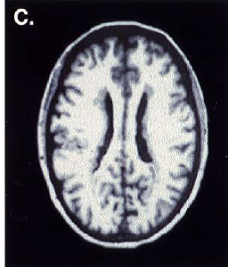

What are this?

polymicrogyria